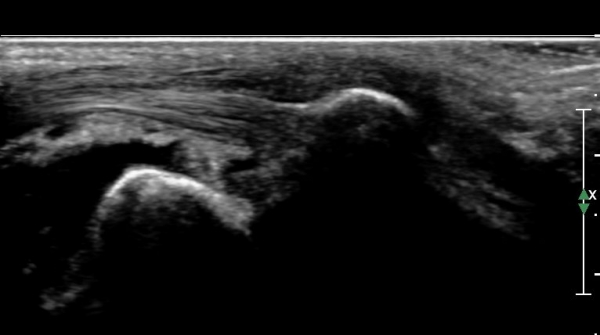

ÃÊÀ½ÆÄ°Ë»ç : ¹ß¸ñ °üÀý Á¾´Ü¸é°Ë»ç¿¡¼­ ¹ß¸ñ °Å°ñ ¿¬°ñÀÌ ¾ã¾îÁ®(thinning) º¸ÀδÙ(»çÁø 1).